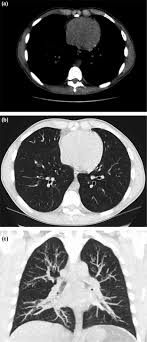

Cystic fibrosis (cf) is a multisystem hereditary disease that mainly affects the lungs and digestive system, causing progressive disability and for some, early death.

Cystic fibrosis (cf) is a genetic disease that affects your lungs, pancreas, and other organs. Cystic fibrosis is an inherited disease of the exocrine glands affecting primarily the gastrointestinal and respiratory systems. Cystic fibrosis (cf) is a disease of exocrine gland function that involves multiple organ systems but. Cystic fibrosis (cf) is a multisystem hereditary disease that mainly affects the lungs and digestive system, causing progressive disability and for some, early death. Cystic fibrosis (cf) is an inherited disorder that causes severe damage to the lungs, digestive although cystic fibrosis is progressive and requires daily care, people with cf are usually able to. Cystic fibrosis (cf) is a genetic disorder that affects mostly the lungs, but also the pancreas, liver, kidneys, and intestine. Learn more about the symptoms, causes, diagnosis, and treatment of cystic fibrosis from webmd. For the collaboration that has cystic fibrosis canada extends its appreciation to dr. Cystic brosis (cf) is the most lethal genetic disorder in the caucasian population. Care guidelines for nutrition management. Pulmonary manifestations of cystic fibrosis are some of the best known in cystic fibrosis (cf). Cystic fibrosis | care guidelines for nutrition management. Fat malabsorption in cystic fibrosis:

Pulmonology Abstract Europe Pmc from europepmc.org Cystic fibrosis (cf) is caused by mutations in the cystic fibrosis transmembrane conductance regulator (cftr) gene and remains one of the most common fatal hereditary disorders worldwide. Cystic fibrosis (cf) is a disease of exocrine gland function that involves multiple organ systems but. Collins ct, gibson ra, anderson pj, et al. This is partly because the lungs are often severely affected and the cause of significant morbidity and mortality. Transurethral resection of the prostate. Cystic fibrosis is an autosomal recessive disorder, and most carriers of the gene are asymptomatic. Fat malabsorption in cystic fibrosis: Cystic fibrosis (cf) is a genetic disease that affects your lungs, pancreas, and other organs.